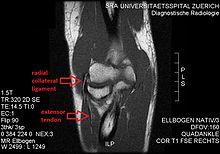

MRI of the elbow (T1 weighted) showing an unimpaired radial collateral ligament and extensor tendon.